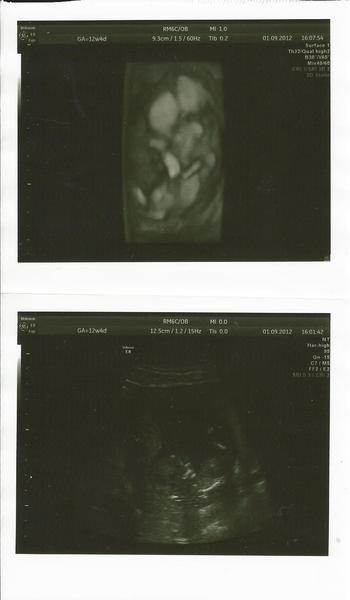

včerajsi 3D ultrazvuk bol uzasny .. sice sa mu nechcelo velmi ukazovat a spinkalo .. ale tesili sme sa ze vsetko je vporiadku .. pridavam svoju fotecku - nase male miminko (skoro 6cm)